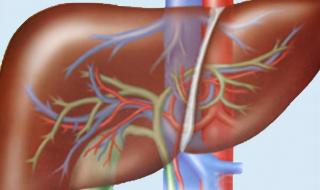

身上有小红点不是乙肝的症状。乙型肝炎,是由乙型肝炎病毒(HBV)感染引起的以肝脏炎性病变为主并可引起多器官损害的一种传染病。本病可广泛流行于世界各国,一年四季均可发病,但多属散发。临床起病缓慢,以亚临床型及慢性型较常见。